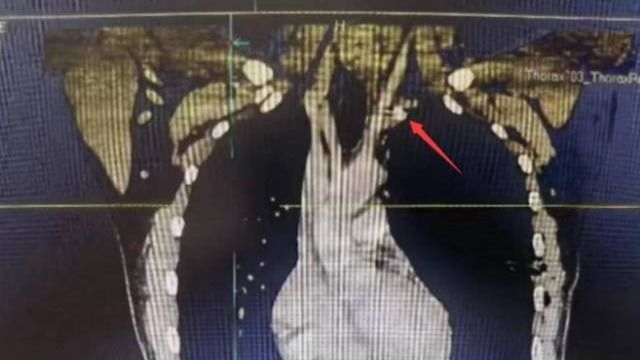

• 【南方日报】中大五院全力急救被金属异物刺穿颈部动脉患者

近日,中大五院胸外科成功为一名“熊猫”血型(B型Rh阴性)的左颈动脉外伤合并气胸的患者实施手术,取出一枚嵌插于左颈总动脉根部的金属异物,并修复了患者血管破口,避免大出血。原来,23岁的徐先生被高速旋转的金属模具碎片射中左侧颈根部,当即出现疼痛、呼吸困难,被紧急送到中大五院治疗。据医院外科主任兼胸外科主...